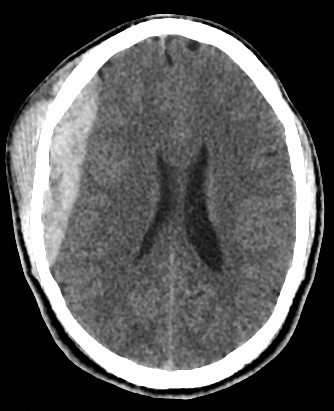

brain CT scan

A brain CT scan, also known as a computed tomography scan or CAT scan, is a non-invasive imaging procedure that uses X-rays to create detailed cross-sectional images of the brain and surrounding structures. It's a common diagnostic tool for evaluating head injuries, strokes, brain tumors, and other neurological conditions. Here's a more detailed explanation: What it is: A brain CT scan uses a series of X-ray beams that rotate around the head, capturing multiple images from different angles. These images are then processed by a computer to create detailed cross-sectional views of the brain, allowing doctors to visualize the brain's structures and identify any abnormalities. The scan can be performed with or without contrast dye, which helps to highlight certain tissues and blood vessels for better visualization. Why it's used: Traumatic brain injuries: CT scans are often the first imaging test used to assess the extent of head injuries and identify potential fractures, bleeding, or swelling. Stroke: CT scans can quickly identify whether a stroke is caused by a blood clot (ischemic stroke) or bleeding (hemorrhagic stroke), guiding appropriate treatment. Brain tumors: CT scans can help detect and assess the size and location of brain tumors. Other neurological conditions: CT scans can also be used to diagnose conditions like hydrocephalus (excess fluid in the brain), aneurysms (bulges in blood vessels), and certain types of dementia. Guiding procedures: CT scans can be used to guide biopsies or other procedures involving the brain. What to expect during the procedure: You will lie on a table that slides into the CT scanner, which is a large, doughnut-shaped machine. The scan itself is painless, but some people may experience slight discomfort from lying still on the hard table. If contrast is used, you may feel a warm or flushing sensation, or a metallic taste in your mouth. The scan typically takes only a few minutes. Risks and Precautions: CT scans involve exposure to radiation, but the risk from a single scan is generally considered low. If you are pregnant, it's important to inform your doctor, as alternative imaging methods may be considered to avoid exposing the fetus to radiation. If you have any allergies, particularly to contrast dye, make sure to inform your doctor.